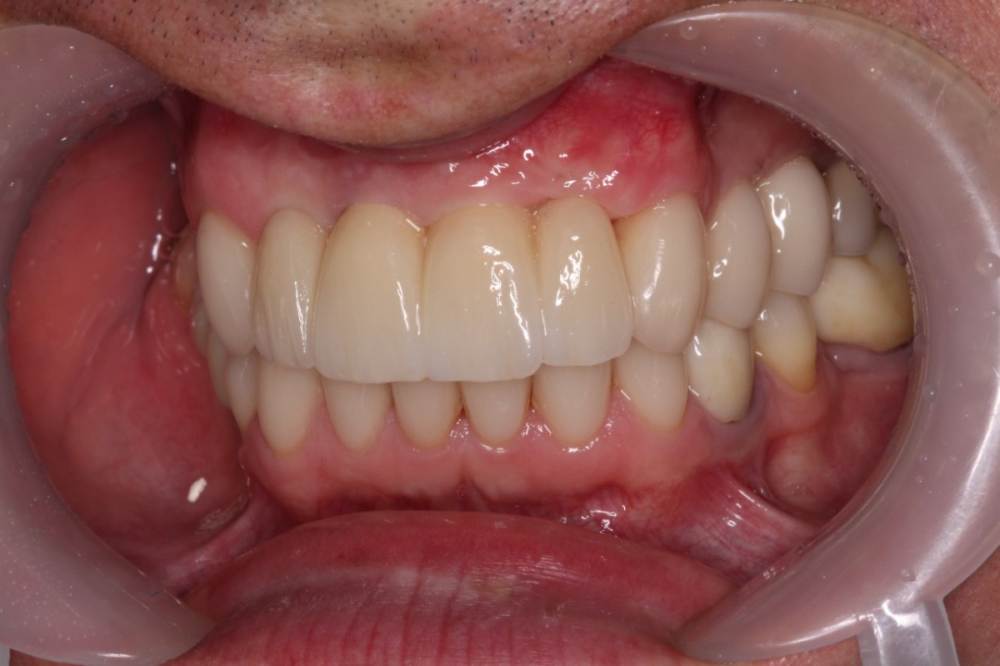

maksimstom Опубликовано 1 сентября, 2021 Автор Поделиться Опубликовано 1 сентября, 2021 Всем спасибо! Результат через 6 мес, 2 пластики десны 4 1 3 Ссылка на комментарий

Irouil Опубликовано 1 сентября, 2021 Поделиться Опубликовано 1 сентября, 2021 Как решили? учитывая исходник - очень внушительно! Ссылка на комментарий

maksimstom Опубликовано 2 сентября, 2021 Автор Поделиться Опубликовано 2 сентября, 2021 Тоннельно 1 транспл окклюзионно, 1 вестибулярно, ждал месяца 4, бугор подрос 1 Ссылка на комментарий